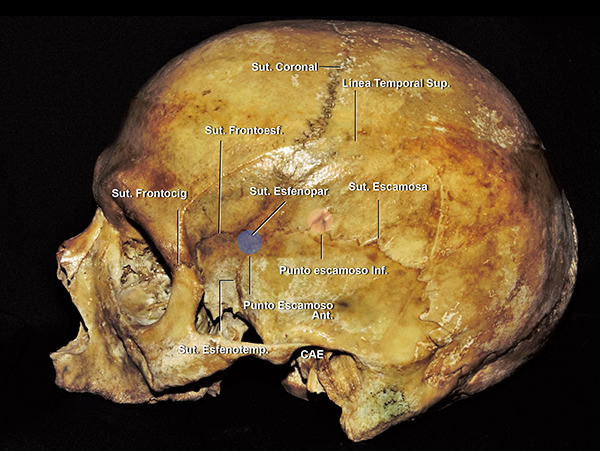

Los puntos microquirúrgicos silvianos tienen su correlación con puntos craneométricos. Los mismo fueron popularizados por Ribas en varias publicaciones.22,23,29 El punto silviano anterior15,17,22,23,25,29 se relaciona en la superficie craneal, con un punto localizado 3 cm detrás de la sutura frontocigomática.23,29 Este punto craneométrico también se lo puede ubicar en el punto más anterior de la sutura escamosa, sitio donde las suturas esfenoescamosa, esfenoparietal y escamosa se entrecruzan. Ribas et al.29 nombró a este punto craneométrico: punto escamoso anterior (Figura 14).

El punto rolándico inferior se ubica 2 cm detrás del punto silviano anterior.29 Se relaciona superficialmente con el punto craneométrico llamado punto escamoso inferior,29 que se localiza en el punto más superior de la sutura escamosa. El punto escamoso inferior también puede ser ubicado 4 cm superior, en línea vertical, a la depresión preauricular. Así la FS se proyecta sobre una línea que conecta el canto lateral ocular, con los puntos escamosos anterior e inferior (Figura 8A).

Figura 14: Vista lateral de un cráneo. El punto escamoso anterior (círculo azul), se localiza 3 cm detrás de la sutura frontocigomática. El punto escamoso inferior (círculo naranja) se ubica en el punto superior de la sutura escamosa. CAE: conducto auditivo externo; Sut: sutura; Sup: superior; Inf: inferior; Ant: anterior; Esfenopar: esfenoparietal; Esfenotemp: esfenotemporal; Frontocig: frontocigomática.